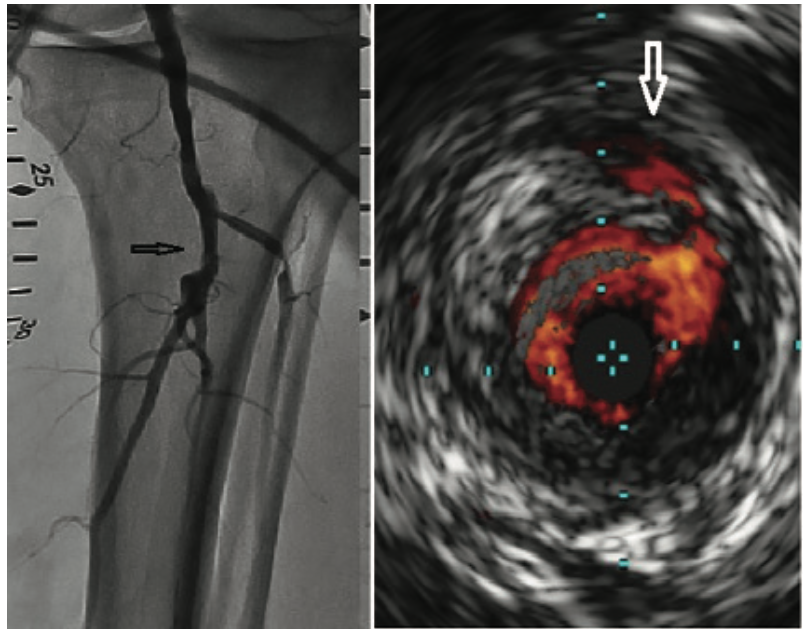

Intravascular ultrasound (IVUS) is an imaging device that provides a 3-dimensional view of what we normally see as a 2-dimensional vascular structure. The device goes over a wire into the vessel, and allows us to see the characteristics inside the vessel looking outward, including the vessel wall, some of the plaque that builds up in the vessel wall, the composition of the plaque, and other characteristics surrounding the vascular structure that are often missed with the 2-dimensional image from angiography (Figure 1). IVUS can be used in any vascular structure. We have been using it in coronary intervention for some time, but we can also use IVUS in the arteries of the lower extremities, in the aorta and other arterial branches, and in the venous system.

When we take a picture of a vessel using 2-dimensional reconstruction, it lacks some of the details necessary for making an accurate assessment in terms of how to proceed and optimize a revascularization procedure. For example, on the arterial side, we often rely on calcium showing up on an x-ray image, but often that calcium is either not visible due to underlying structures like bone, muscle, or tissue, or it is not completely captured in the angiographic view. IVUS allows us to better see the degree of calcium in the vessel. It is the same issue for a lesion. In some views, a lesion can look moderate or mild. In some views, a lesion can look severe. If you don’t take the right view, then you may be unable to classify the severity of that lesion. An intravascular imaging device allows us to see the severity of the actual disease compared to what the vessel should look like when evaluated with a normal reference. We can understand the composition of the disease and how to treat it. Intravascular imaging is in an evolving role for the lower extremity space. The question is how do we use it, not necessarily to replace angiography, but to complement angiography, and to provide a more meaningful and complete picture in regards to determining how best to revascularize and optimize treatment for our patients with peripheral vascular disease.